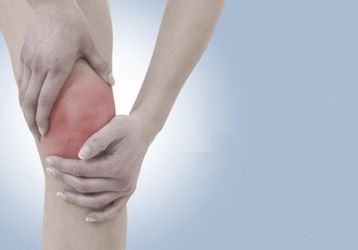

Деформирующий артроз коленного сустава 1, 2, 3 степени: причины, симптомы, лечение

Что представляет собой деформирующий артроз коленного сустава, по каким причинам появляется заболевание. Симптомы и признаки, лечение 1,2,3 стадий.